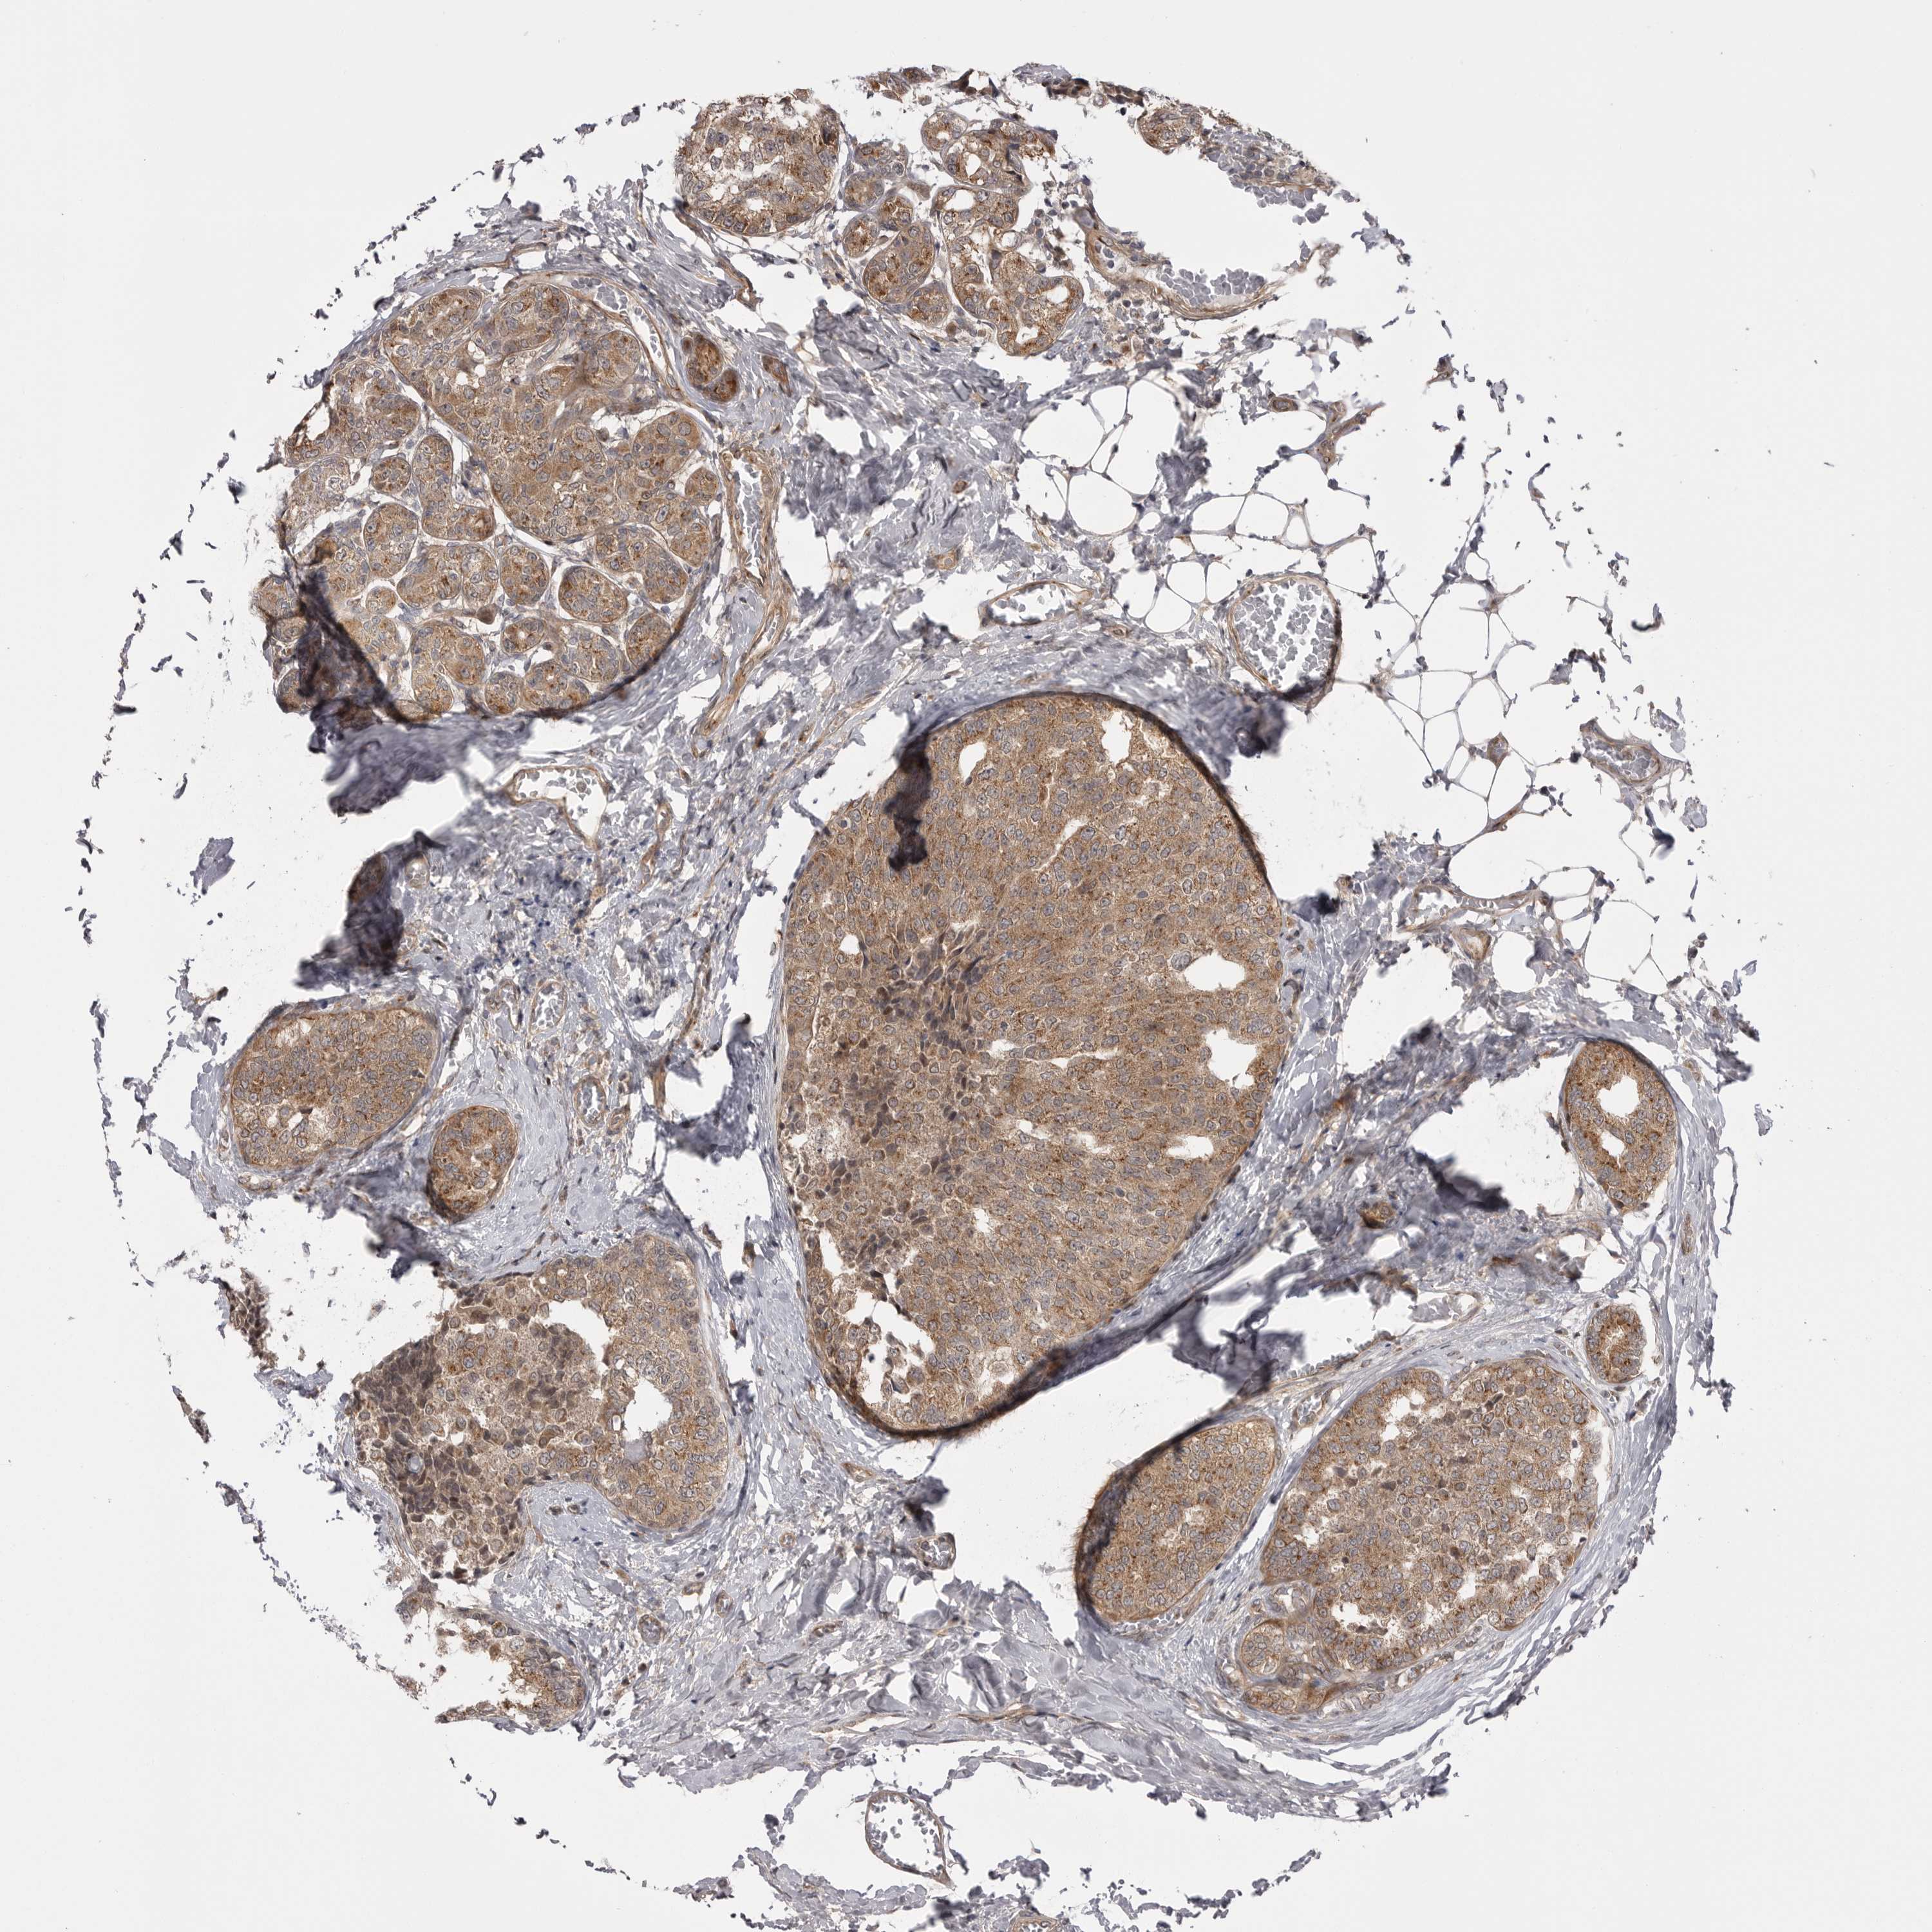

CANCER BREAST CANCER Show tissue menu

BRCA TCGA BRCA VALIDATION PROTEIN EXPRESSION